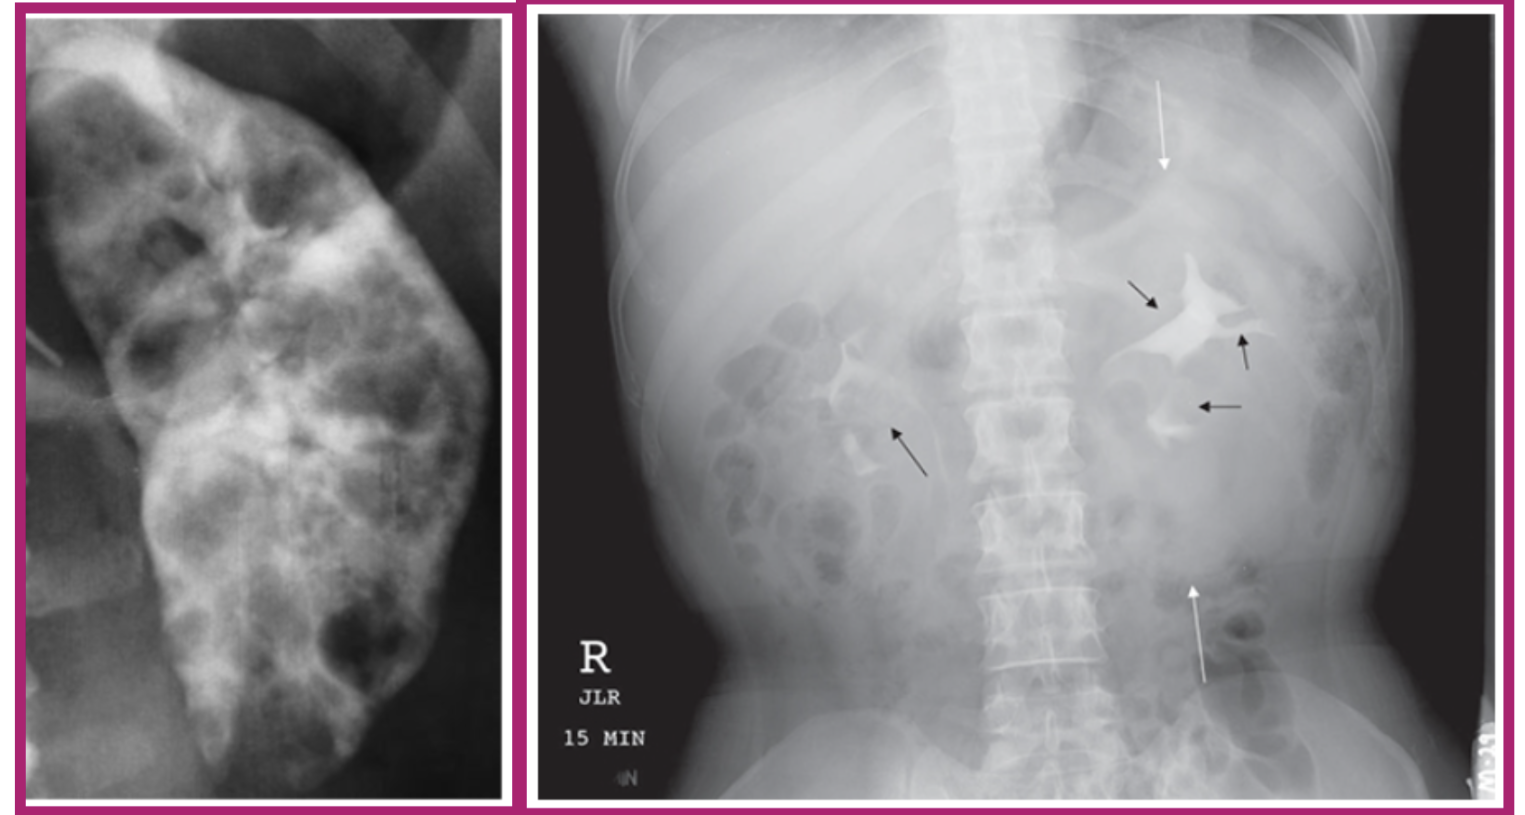

what pathology does this image show

polycystic kidney disease